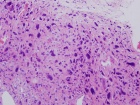

46 year old male noted some fullness in his right thigh about 5 months prior to presentation. Noticed some tense feelings in his thigh over the past month.

Zoom image: Cell stain Cell stain.